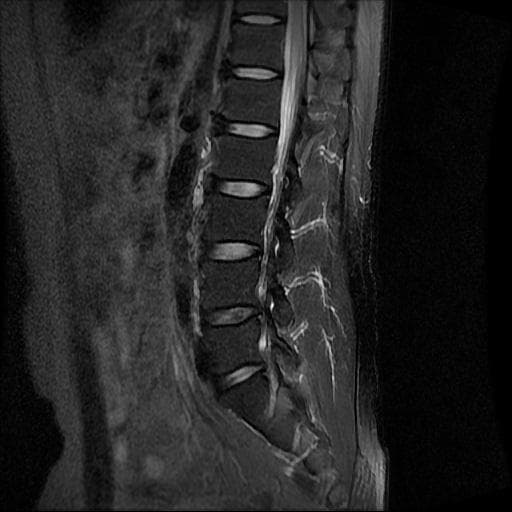

허리 MRI 디스크 상태 분석 부탁드립니다

검진 차 MRI찍었는데 분석 부탁드립니다.

건협에서는 관리해야 된다는데 디스크 협착이나 팽윤 등이 있는 상태인지 궁금합니다.

우선 현재로썬 사진만으론 판단을 하기에 제한이 되지만 사진상 디스크 상태는 심해보이지 않습니다.

요추부위의 하부 에서 약간의 팽윤이나 돌출로 의심해볼수 있는 정도이지만, 정확한 상태는 관련 전문의에게 진료시 문의를 하시는 것을 추천드립니다.